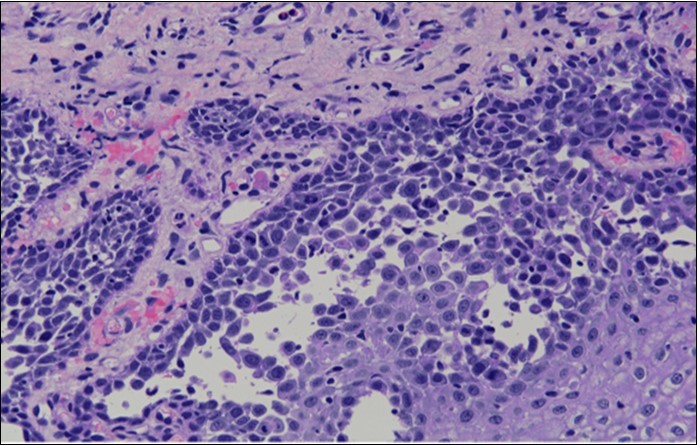

She was discussed at the hospital cyto-pathology conference to clarify the diagnosis. The original cytological smear specimen was reviewed, with features of bi-nucleation and koilocytosis consistent with LSIL. The cervical biopsy was also reviewed, confirming typical features suggestive of cervical pemphigus. (Figure 4a, Figure 4b, Figure 4c)

Figure 4b.Prominent acantholysis identified

Prominent acantholysis identified

Figure 4c.Well vascularised dermal papillae with residual basal layer giving rise to tombstone appearance

Well vascularised dermal papillae with residual basal layer giving rise to tombstone appearance